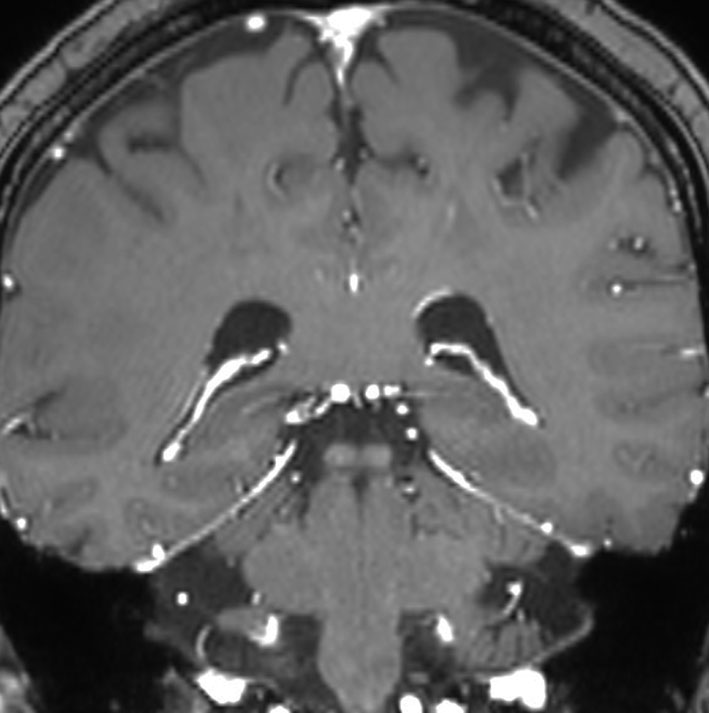

放射線治療後の再燃や脳壊死に対する脳外科手術

左側頭葉への腎癌の単発転移です。症候性てんかん(失語症発作)で発見され,定位放射線治療を受けたのですが,数ヶ月後に脳浮腫が高度となり失語症が悪化しました。コアになっている円形の転移腫瘍の周囲に放射線による脳壊死を疑いました。2時間ほどの開頭手術で,右側のガドリニウム増強されているところだけを摘出しました。

手術1年半後の画像です。症状はなくて元気にお暮らしでした。新たな脳転移はありません。